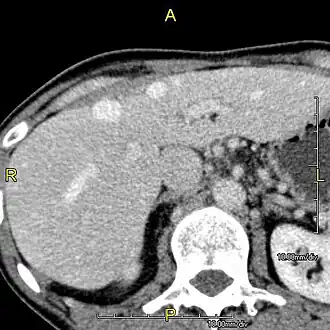

Left lobe liver tumor

The liver is a vital organ and supports almost every other organ in the body. Because of its strategic location and multidimensional functions, the liver is prone to many diseases.[58] The bare area of the liver is a site that is vulnerable to the passing of infection from the abdominal cavity to the thoracic cavity. Liver diseases may be diagnosed by liver function tests–blood tests that can identify various markers. For example, acute-phase reactants are produced by the liver in response to injury or inflammation.